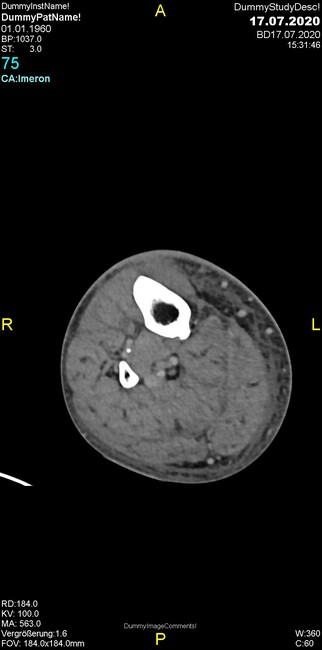

Um welche Modalitäten handelt es sich?

- Röntgen p.a. und lateral, CT coronar Knochenfenster, CT axial Weichgewebsfenster

- Röntgen p.a. und oblique, CT coronar Knochenfenster, CT axial Weichgewebsfenster

- Röntgen p.a. und lateral, CT sagittal Weichgewebsfenster, CT coronar Knochenfenster

- Röntgen p.a. und oblique, CT sagittal Knochenfenster, CT coronar Weichgewebsfenster

- Röntgen p.a. und lateral, CT coronar Weichgewebsfenster, MR axial

Was fällt in der Projektionsradiographie auf?

- Verdichtung im Recessus suprapatellaris

- Aufhellungslinie in Projektion auf die Femurkondylen

- Erhöhter tibialer Slope

- Hypertransparenz tibial

- Subluxationsstellung im Kniegelenk

Was trifft auf den Befund zu?

- Der Befund beschränkt sich auf den Knochen.

- Es besteht hochakuter Handlungsbedarf.

- Der Befund ist tendenziell benigne.

- Der Befund ist tendenziell maligne.

- Der Befund weist einen Zusammenhang zum Patientenalter auf.

Was fällt in der CT im Knochenfenster auf?

- Mediale Gelenkspaltverschmälerung

- Dezente Erosion der fibulären Kortikalis

- Frakturspalt der lateralen Tibiametaphyse

- Weichgewebskalzifikationen lateral angrenzend an den Gelenkspalt

- Osteolyse der Tibiametaphyse unter Beteiligung der Kortikalis